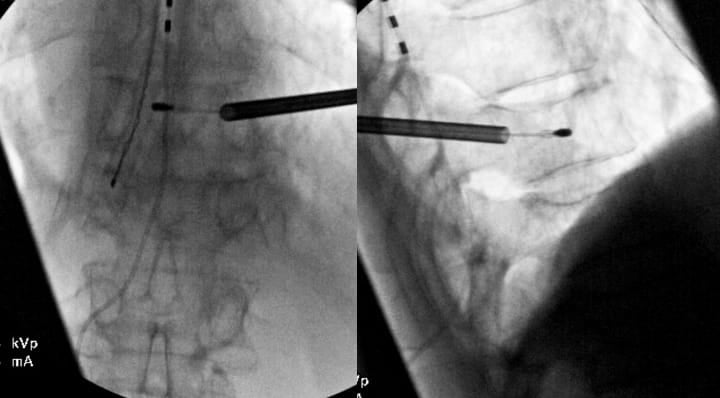

Patients with scoliosis present unique challenges due to sagittal plane deformity but also potentially rotational deformities and altered vertebral anatomy. The rotational component displaces pedicles from normal positions, requiring careful three-dimensional anatomy analysis before the procedure. Pre-procedural CT with multiplanar reconstructions is helpful for trajectory planning. The convex side often provides less challenging access due to pedicle orientation. To obtain accurate (AP) and lateral views, it is more effective to rotate the bed rather than the C-arm. This approach facilitates the acquisition of true lateral images, particularly when utilizing C-arm equipment that has a limited rotation capability of 90 degrees (Figure 5).